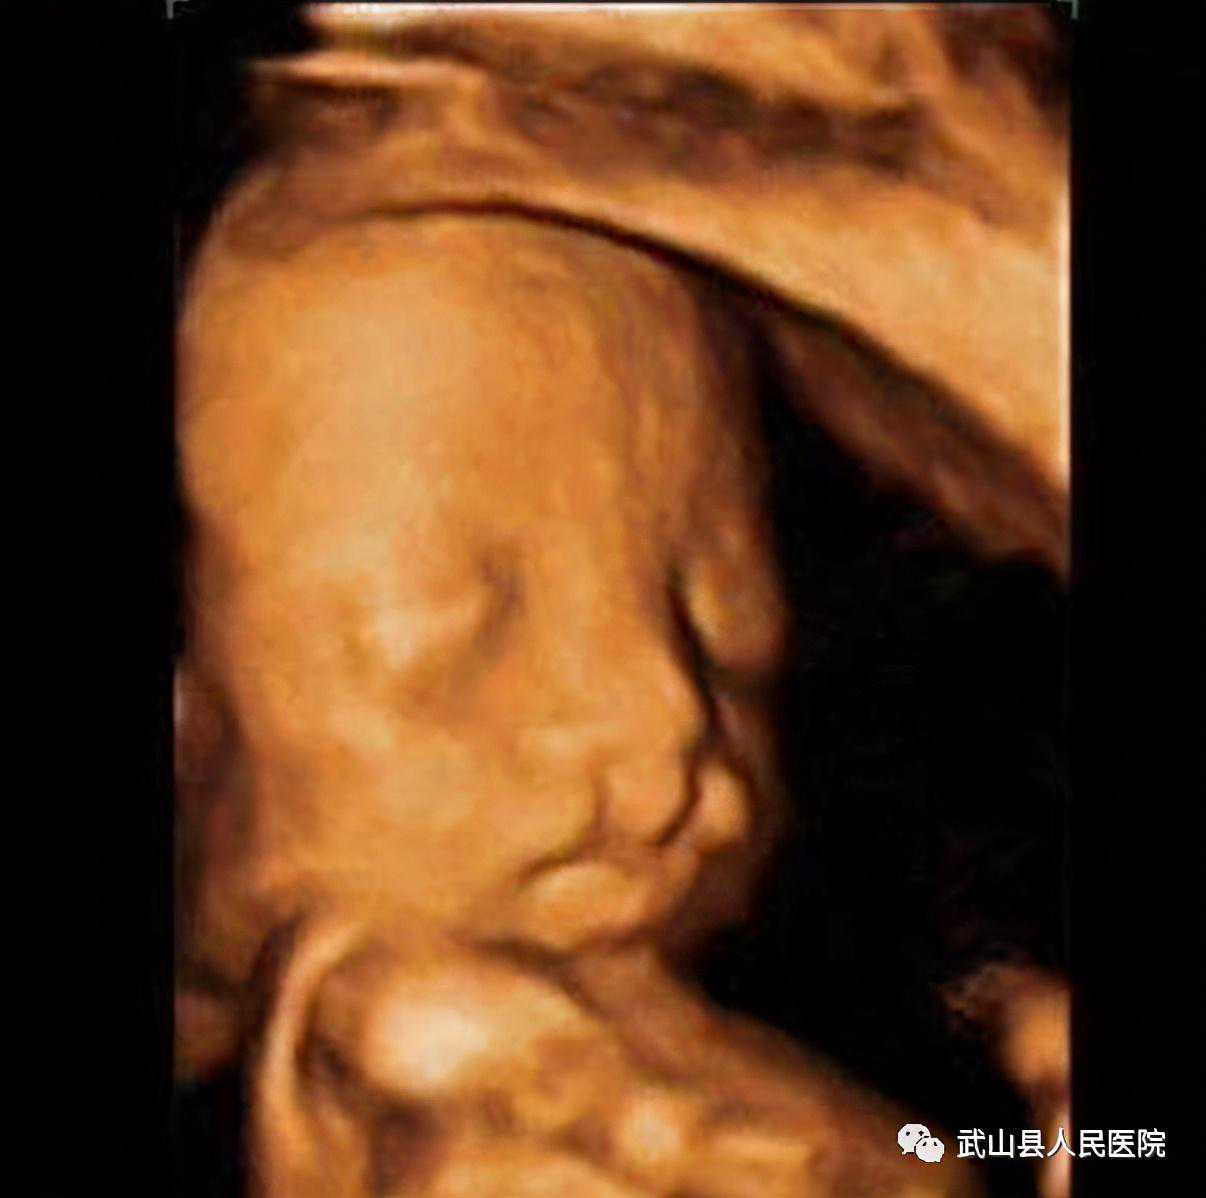

1.孕11周----13+6周胎儿NT检查

明确妊娠胎儿数目、羊膜囊及绒毛膜囊数目;生长参数测量评估胎儿大小;NT值(颈项透明层厚度)测量及鼻骨观察判断胎儿染色体异常风险;筛查胎儿颅脑、肢体等严重的结构异常。